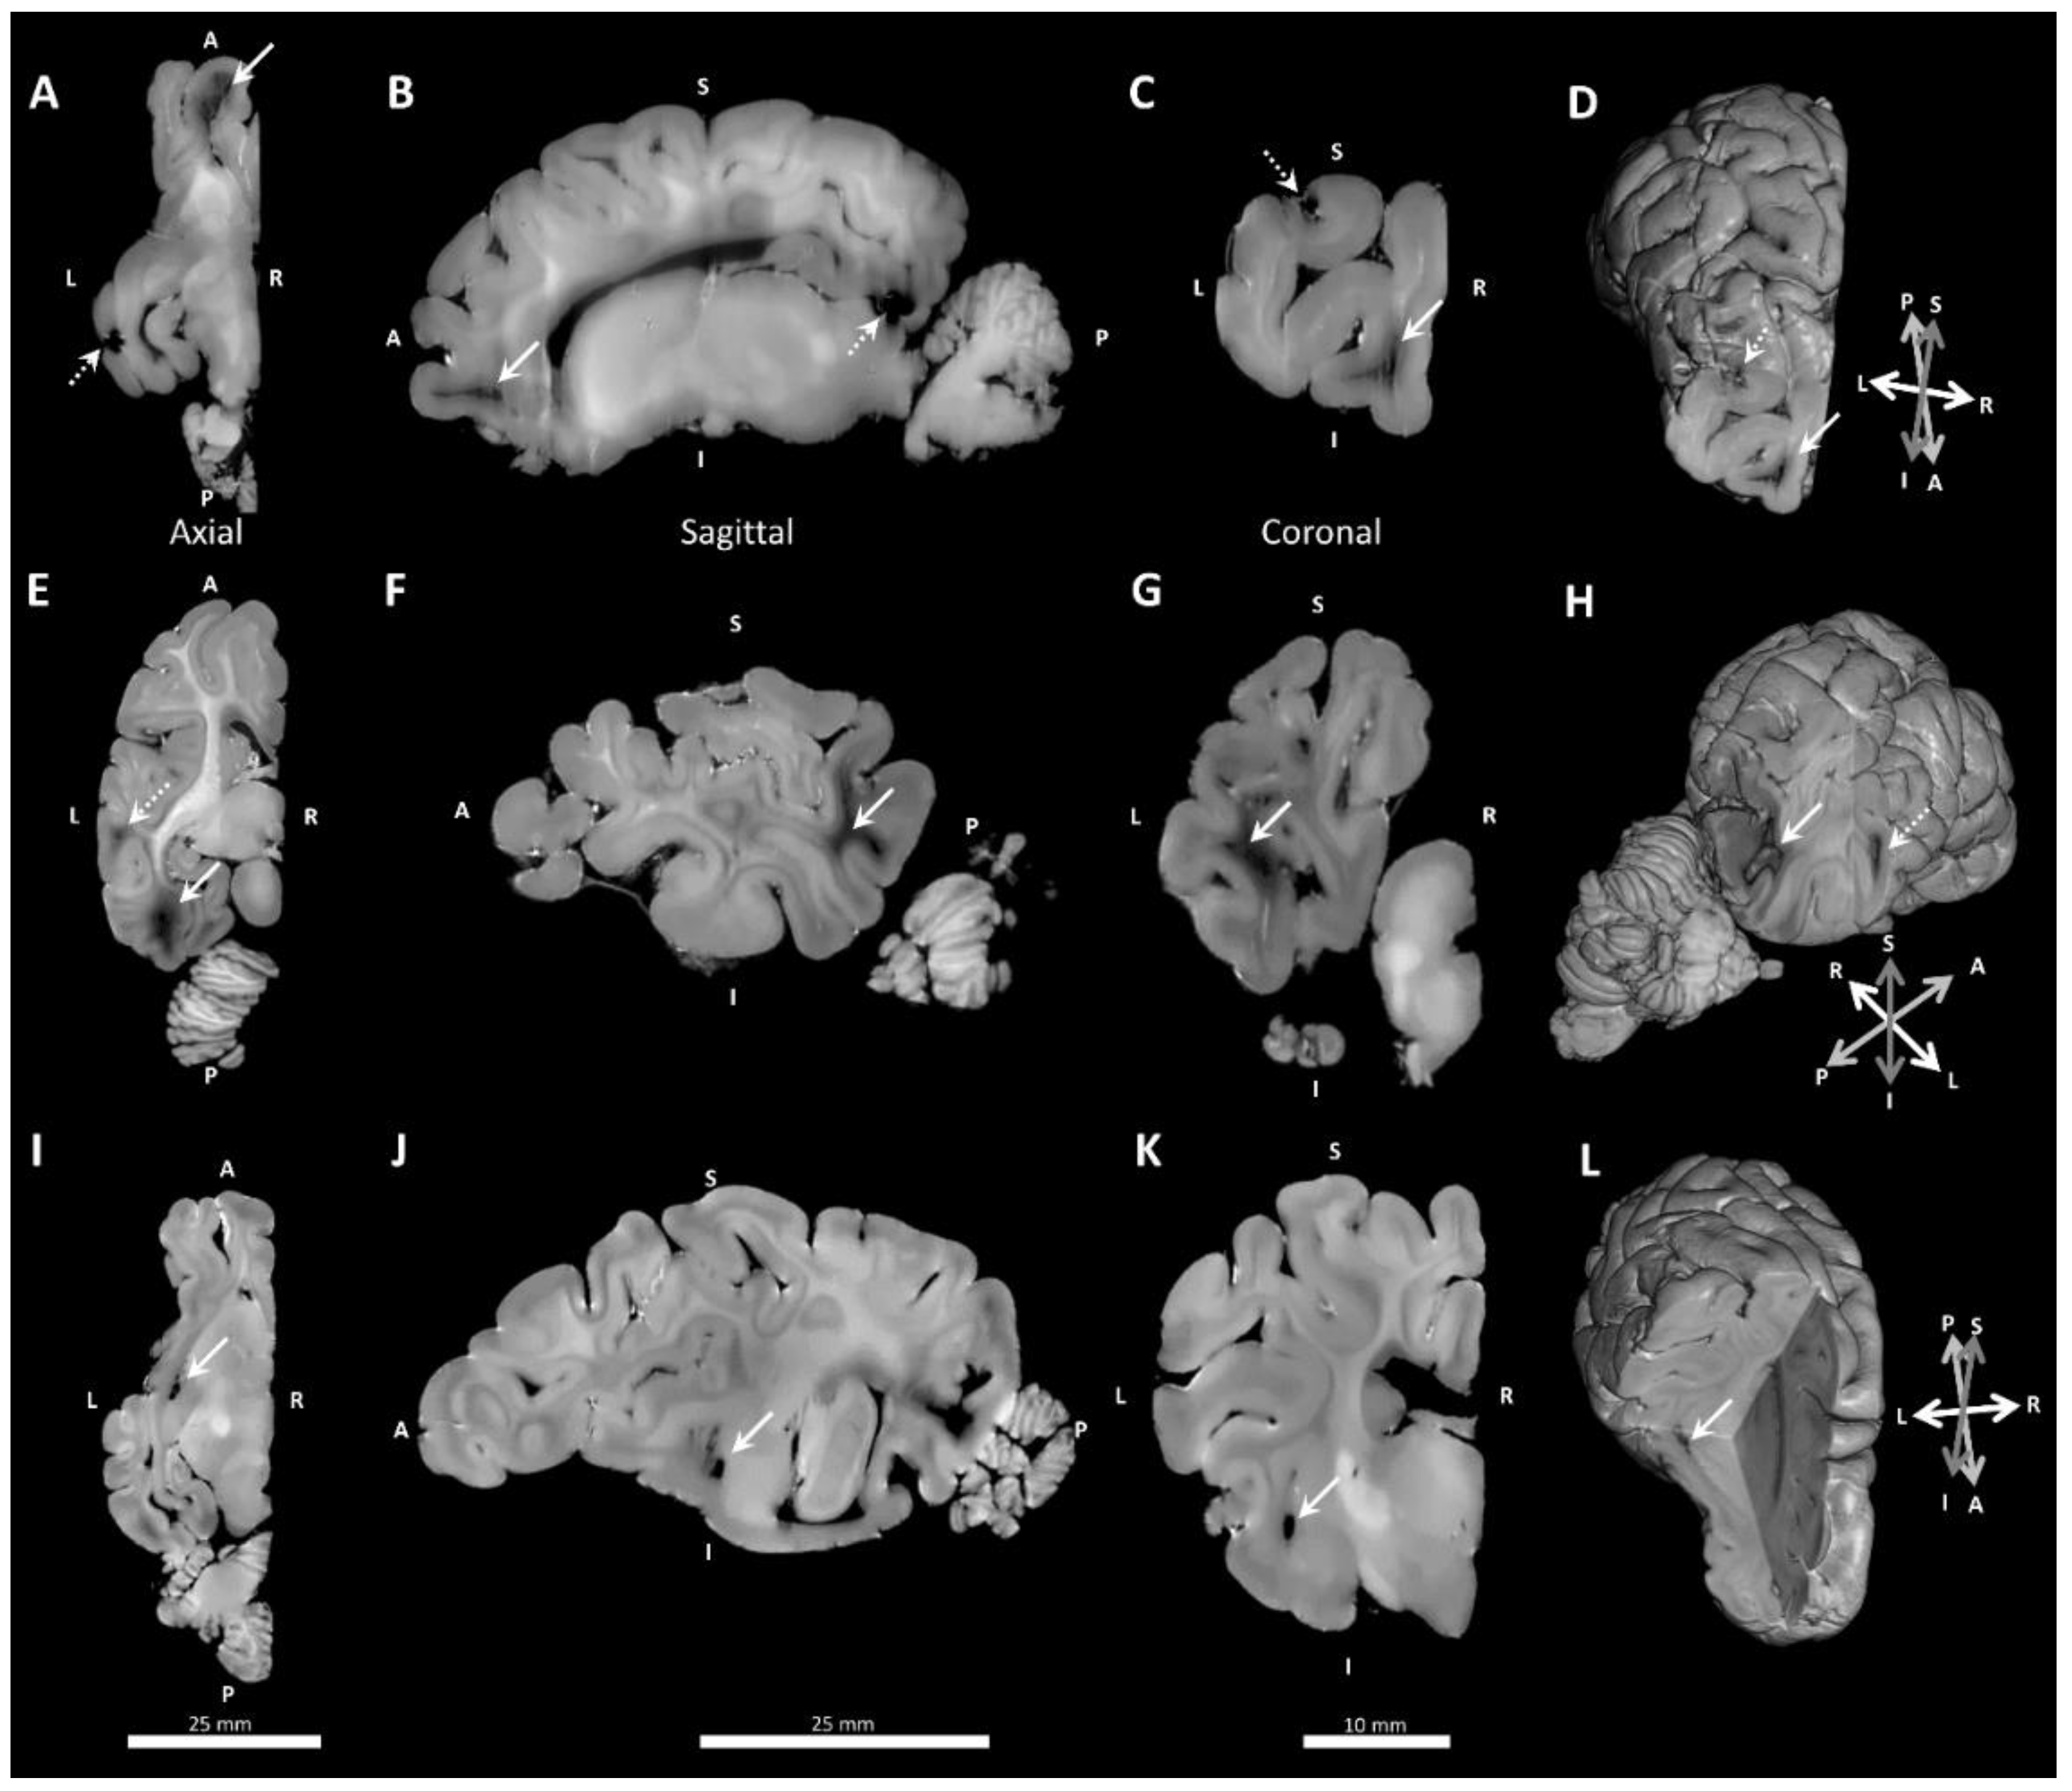

3.3. Neuropathology

Two main types of white matter pathology were observed in MRIs: 1) white matter lesions in the frontal cortex (Figure 7A–D), temporo-parietal and occipital cortex (Figure 7E–H); and 2) cystic dissolution in the lateral boundary anterior to the amygdala and medial to the parahippocampal gyrus (Figure 7I–L). Cystic lesions were differentiated from large deeply penetrating blood vessels based upon size and shape, and were confirmed with histology in the two control fetal lambs that had MRI evidence of cystic lesions (Table 4). Independent analysis of T1- and T2-weighted images showed that the same white matter lesions were detected using either imaging sequence, except in one case, where T2-weighted image missed a frontal cortex lesion due to trapped air, appearing to be similar to white matter on initial inspection.

Figure 7.

Example lesions in T1-weighted MRI images shown in orthogonal planes and with 3D rendering. (A–D) Frontal cortex white matter lesions (solid white arrows) and examples of susceptibility artefacts due to undissolved gas (stippled arrows). (E–H) Temporal lobe cortex lesion (stippled arrow) and occipital cortex white matter lesion (solid white arrow). (I–L) Deep cystic lesions (solid white arrows). Abbreviations: L, Left; R, Right; I, Inferior; S, Superior; A, Anterior; P, Posterior.